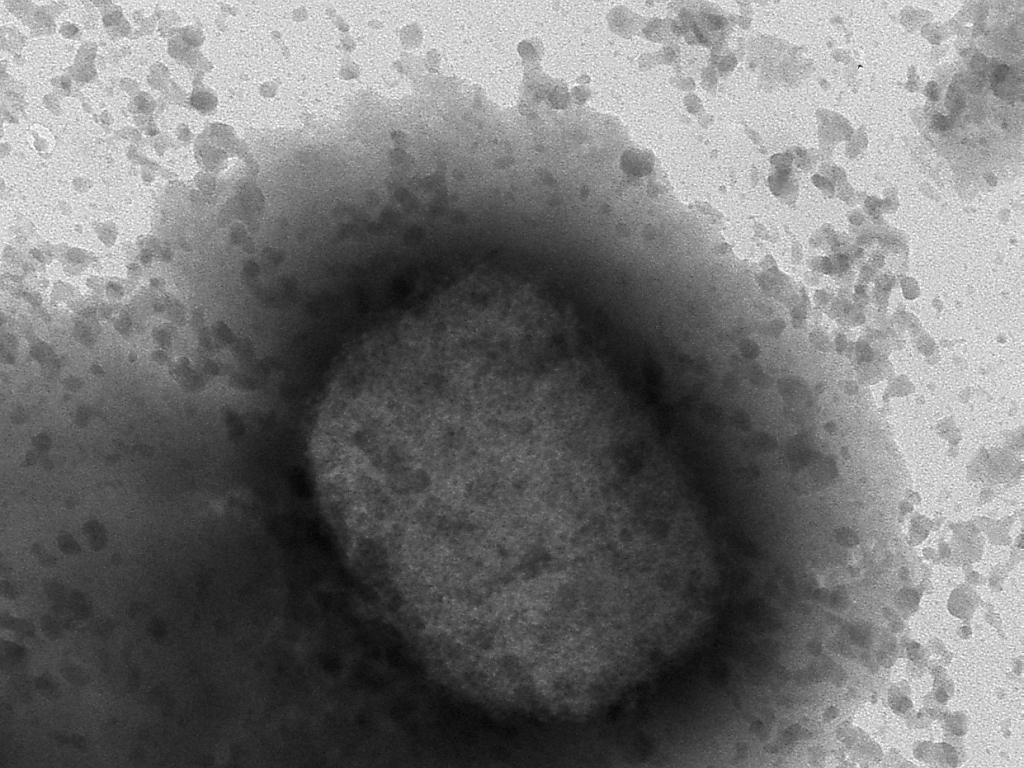

La variole du singe est une maladie infectieuse causée par un virus qui se transmet de l'animal à l'humain, mais qui peut aussi se transmettre d'humain à humain. (© KEYSTONE/AP)

La variole du singe est une maladie infectieuse causée par virus qui se transmet de l'animal à l'humain, mais qui peut aussi se transmettre d'humain à humain. Ces derniers jours, la présence de ce virus rare, endémique dans certaines régions d'Afrique, a été rapportée dans plusieurs pays européens, ainsi qu'aux Etats-Unis.